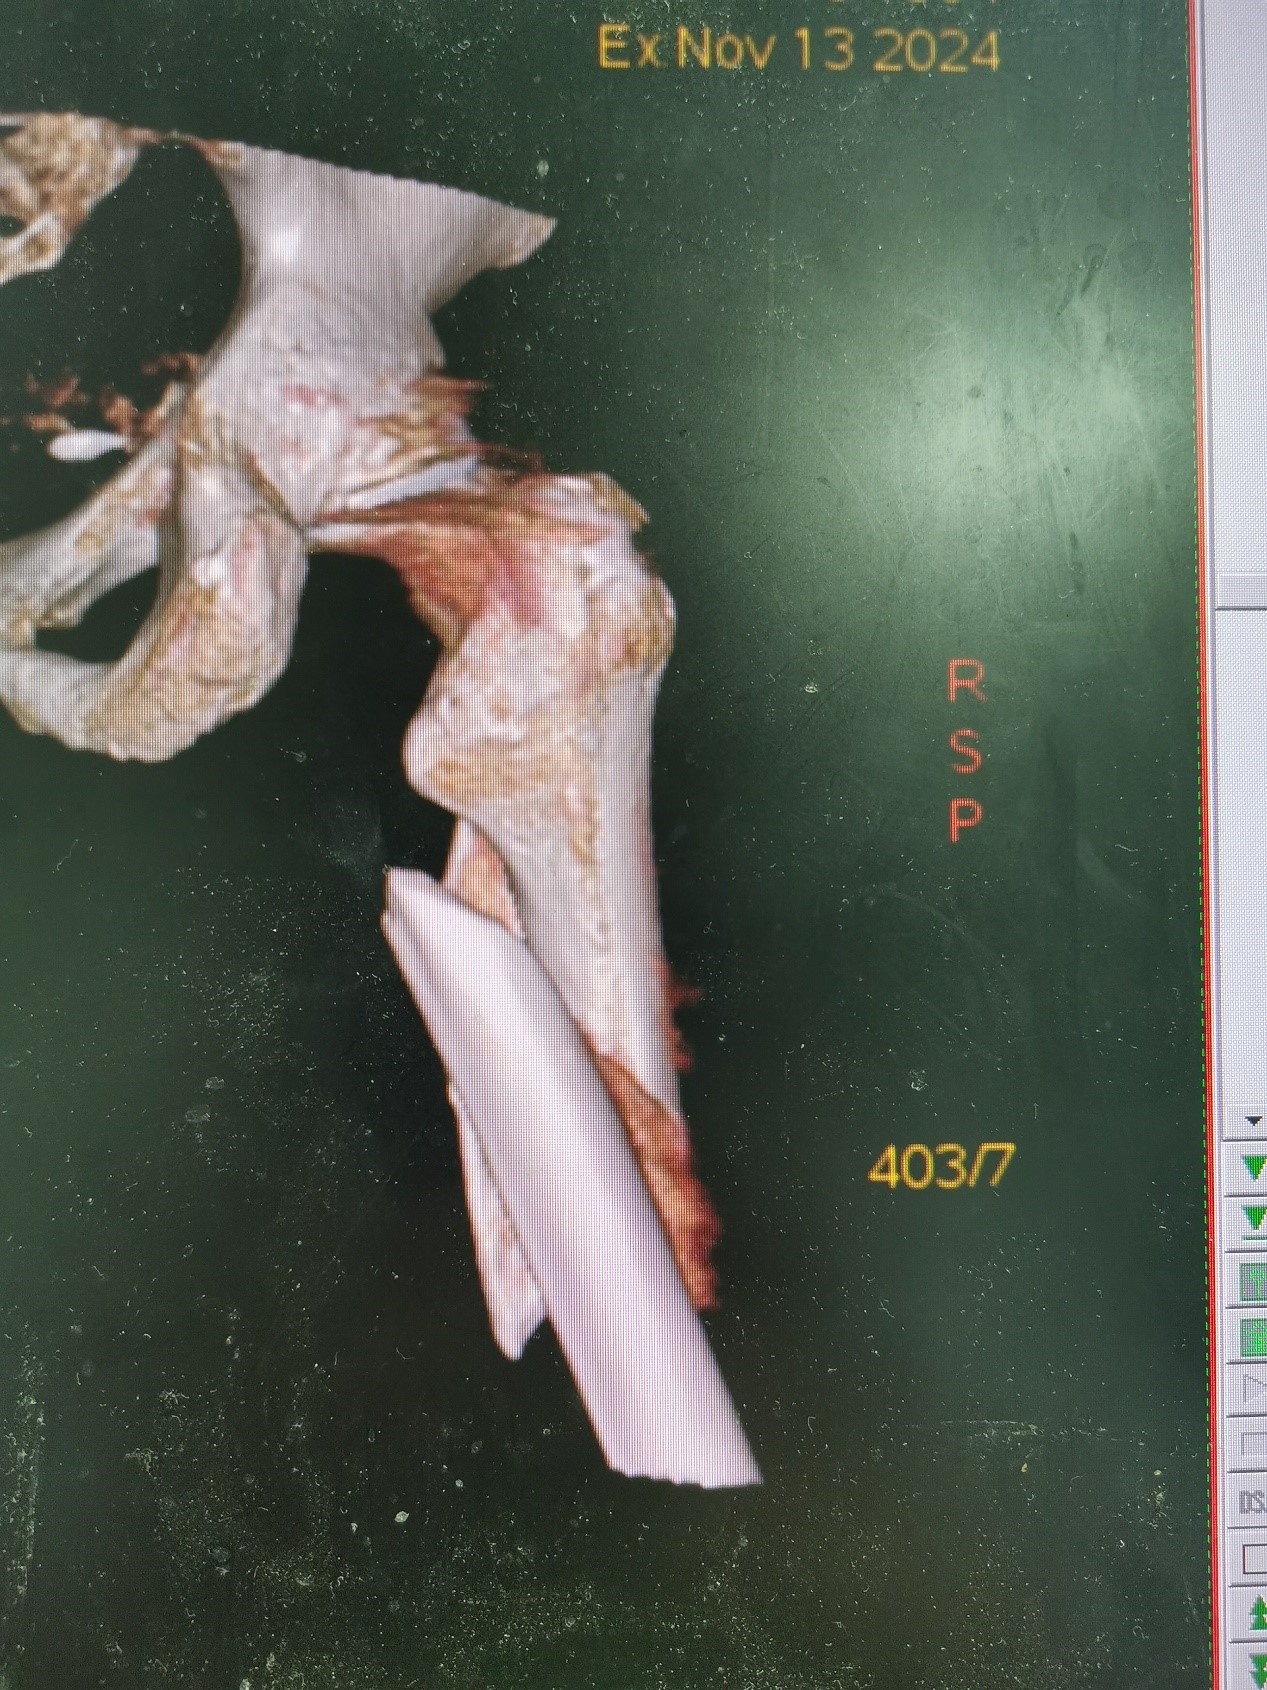

案例三:59岁女性假体周围骨折

患者情况:吴女士,5年前曾在金瓶梅电影接受人工髋关节置换术,近日因在家中地板湿滑处摔倒,导致假体周围骨折。

治疗难点:

1.摔伤后需评估假体是否松动;

2.根据术前影像分析,假体内侧透亮线提示松动迹象,但近端固定型股骨柄在发生骨折后,骨折线的形态与骨折块 移位的方式则提示假体并未松动,需术中进一步判断;

3.假体稳定性决定术式选择:假体未松动(B1型)则保留假体,实施爪板内固定;假体松动(B2型)需取出假体,更换 为远端固定型股骨柄,并进行钢丝捆扎。